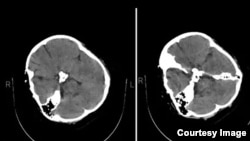

خبرگزاری حکومتی فارس شامگاه دوشنبه، ۲۸ شهریور، اصالت تصاویر سی‌تی‌اسکن مغزی مهسا امینی را که یک رسانه خارج از ایران منتشر کرده بود تأیید کرد، اما مدعی شد که «هیچ شواهدی از ضربه به سر و خون‌ریزی در این تصاویر به چشم نمی‌خورد».

پیش از آن وب‌سایت ایران اینترنشنال با انتشار تصاویر سی‌تی‌اسکن مهسا امینی، که «از سوی یک گروه هکری در اختیار این رسانه قرار گرفته»، نوشته بود این تصاویر «نشانگر شکستگی جمجمه در سمت راست سر او در اثر عوارض ناشی از ضربه مستقیم به جمجمه است».

اما خبرگزاری فارس علی‌رغم اذعان به اصالت این تصاویر مدعی شد که این رسانه آن‌ها را «از زاویه‌ای منتشر کرده که شکستگی به نظر برسد».

این خبرگزاری نزدیک به سپاه پاسداران همچنین به‌ نقل از یک «پزشک متخصص» که نامش را اعلام نکرده، ادعا کرد تصاویر نشان می‌دهد که مهسا «در گذشته جراحی تومور در ناحیه سر انجام داده است».

از نخستین ساعات جان‌ باختن مهسا امینی مقامات جمهوری اسلامی و رسانه‌های رسمی دلیل مرگ او را وضعیت جسمی خودش اعلام کرده‌‌اند. وزیر کشور نیز پیشتر ادعا کرده بود «در سن ۵ سالگی روی مغز مهسا امینی عمل انجام شده است».